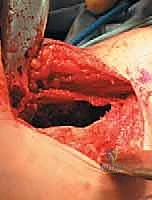

* التكوين النسيجي: لا يحتوي على سائل صافٍ، بل يحتوي على مساحات كيسية متعددة مملوءة بالدم. من الناحية المجهرية، هذه المساحات ليست أوعية دموية حقيقية (تفتقر للبطانة الوعائية)، بل تفصلها حواجز ليفية تحتوي على خلايا عملاقة (Giant Cells) وعظم غير ناضج. هذا التمييز النسيجي حاسم لفهم سبب نزيفها الشديد أثناء الجراحة وطبيعتها العدوانية.

صورة مجهرية توضح الفحص النسيجي لكيس العظم المتمدد (ABC)، حيث تظهر الحواجز الليفية والخلايا العملاقة التي تحيط بالمساحات المليئة بالدم، وهو ما يفسر السلوك العدواني الموضعي لهذا النوع من الأكياس.